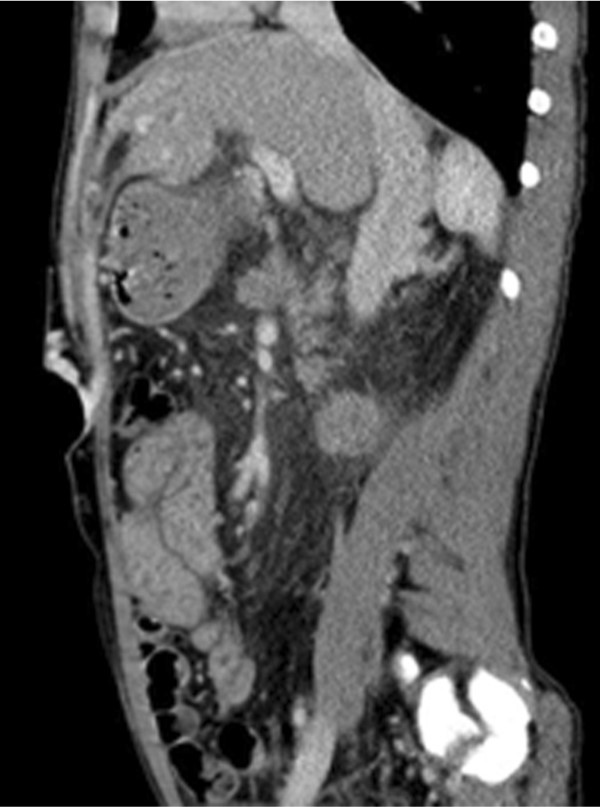

초음파 검사에서 간경화소견, 비장비대와 복벽에 확장된 혈관구조물이 발견됨. 복부 CT상 문맥고혈압에 의한 소견으로 좌문맥과 연결된 제대정맥이 관찰되며 복벽에 확장된 제대정맥류가 보임. 제대정맥류는 천복벽정맥 (superficial epigastric vein)을 통해 체정맥으로 배출되고 있음 (Fig. 1A, 1B).

Fig. 1.

A-B. MIP image and sagital view of CT scan show recanalized umbilical vein supplying umbilical varix in the abdominal wall. The umbilical varix drains into the superficial epigastric vein.